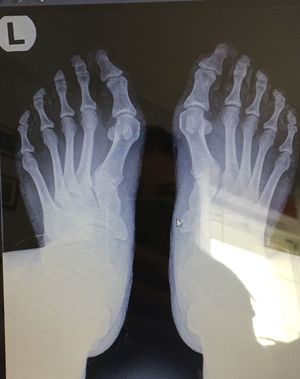

Diagnosis?

Hallux Valgus

Hallux valgus?

I think it is halux valgus

Hallyx Valgus. Aka: a bunyon

From the shape of ankle it is knock ankle or halux valgus but isnt it an osteophit there 1st phalnx both of ankle